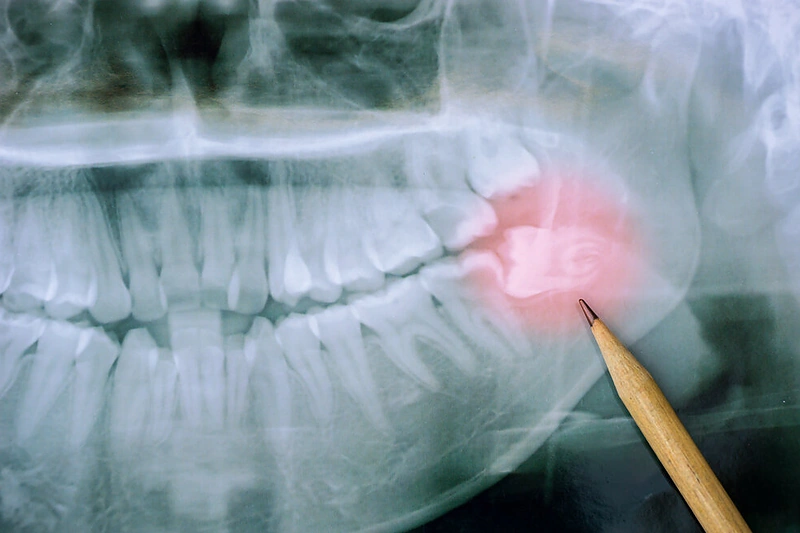

Manoma, kad evoliucijos eigoje protinių dantų neturėtų likti. Dėl pasikeitusių mitybos įpročių, daugėjant termiškai apdoroto maisto, kurio nereikia graužti ir stipriai kramtyti, mažėja žandikaulis, nes kaulinis audinys greičiau nei dantys prisitaiko prie pokyčių. Tačiau dėl vietos trūkumo vis dažniau ir protiniai dantys lieka neišdygę arba jie išdygsta tik dalinai.

Ievos Gendvilienės teigimu, protiniai dantys yra šalinami dėl įvairių priežasčių: dėl to, kad yra nepagydomai pažeisti, netaisyklingai išdygę, aplink juos kaupiasi minkštasis apnašas, formuojasi apydančio audinių uždegimai, pūlynai (kai pūlių prisirenka į minkštųjų audinių tarpraumeninius tarpus), dėl jų formuojamų cistų, gretimų dantų gadinimo, ortodontiniu tikslu, kartais net dėl navikinių procesų. Kiekvienu atveju, ar dantis reikia šalinti ir kada geriausia tai atlikti gydytojas aptaria su pacientu individualiai.

Labai svarbu žinoti, kad kuo ilgiau protiniai dantys išlieka burnoje, tuo didesnė rizika atsirasti patologijai, taip pat dėl šaknų formavimosi, gretimų struktūrų bėgant laikui sudėtingėja ir jų šalinimo procedūra.